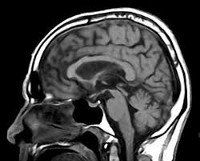

• МРТ головного мозга. Выявляет расширение III желудочка, атрофические изменения среднего мозга, базальных ганглиев, премоторных зон лобной коры и височных областей. Позволяет исключить внутримозговую опухоль, энцефалит, рассеянный склероз, инсульт.